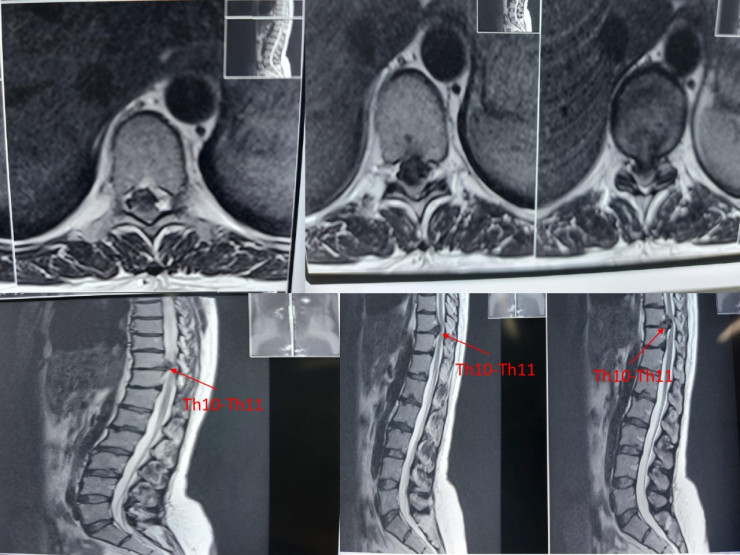

Алматинские нейрохирурги успешно провели сложную операцию пациентке с редкой патологией, передает корреспондент Tengrinews.kz. В отделении спинальной нейрохирургии городской клинической больницы № 7 проведена операция по микрохирургическому удалению грыжи диска грудного отдела позвоночника.

Фото предоставлено пресс-службой ГКБ № 7

"Грыжа грудного отдела возникает, когда фиброзное кольцо разрывается в результате травмы или постепенного истончения и разрушения стенок. В образовавшиеся полости проникает студенистое ядро. Развивающаяся деформация (выпячивание позвоночного диска) приводит к защемлению нервных окончаний спинного мозга и нарушению кровообращения в спинномозговом канале", - пояснили специалисты.

По словам заведующего спинальным нейрохирургическим отделением № 1 ГКБ № 7 Бахыта Аглакова, пациентку продолжительное время беспокоили постоянные ноющие боли в спине, слабость в нижних конечностях, онемение с уровня пупка и обеих ног. Она с трудом передвигалась по дому.

"Операция выполнена на высоком уровне. В послеоперационном периоде нижний парапарез регрессировал полностью, пациентка передвигается самостоятельно, боли в грудопоясничном отделе позвоночника купировались. Чувствительные нарушения также регрессировали", - рассказал Аглаков.